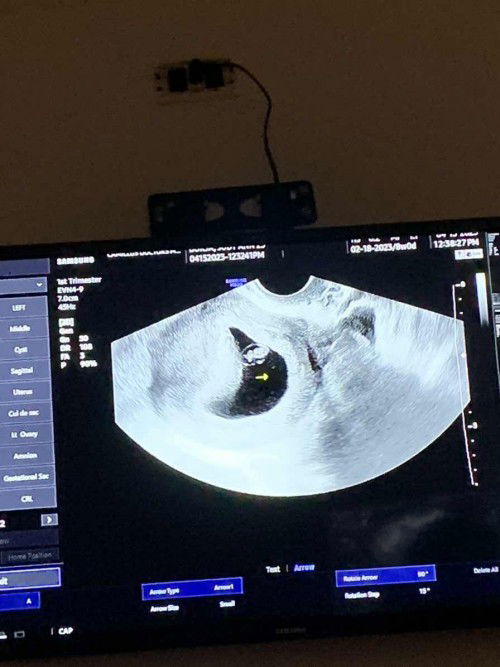

Hello normal lang ba na may white creamy discharge? wala naman amoy. 9 weeks preggy po parang tamod lang ng lalake. Tapos parang normal lang, wala ako sintomas ng pagbubuntis. As in normal lang. kht sore breast nawala din. Pero nakapag trans v na ako eto sya oh. May chance pa ba na makunan ako kht di naman dinudugo. Haysss. Natatakot lang ako. Iniinom ko naman mga vitamins ko.